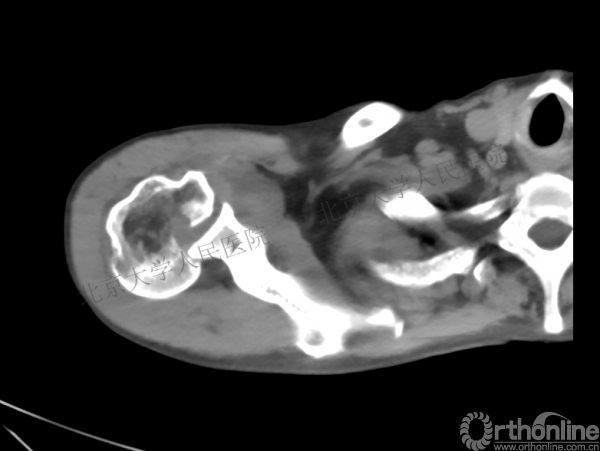

2.CT*—评估缺损大小及关节盂情况

CT检查

1.右肱骨近端骨折

2.右肩关节后脱位